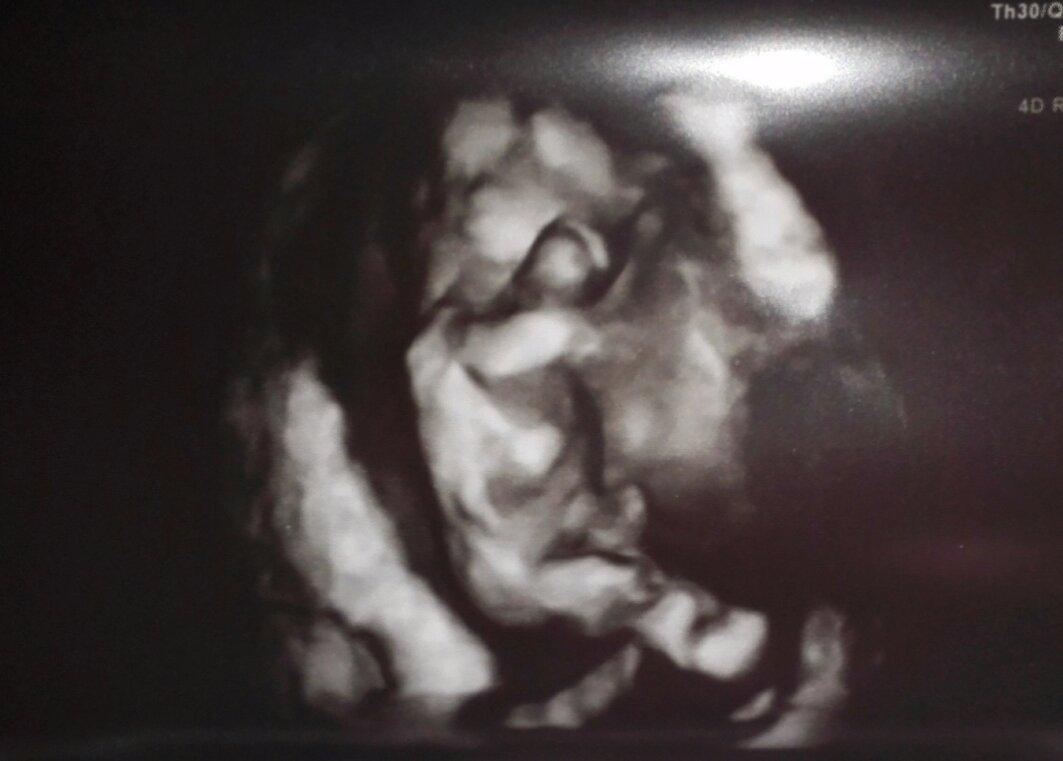

Pincola foto je z 24tt

UFO z vesmíru

tys tak jednou taky vypadal(a),a,možná to trvá i dál😀 😀 😀

Teď vidím, že se mi to seřadilo naopak, takže první fotka je 12. týden a pak dvě z 13. týdne.